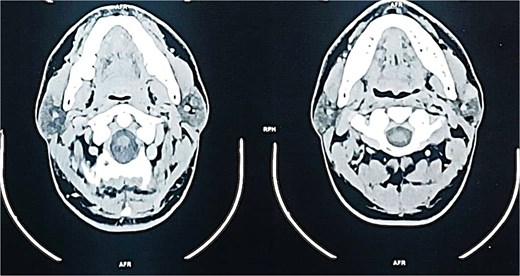

A contrast-enhanced computed tomography (CT) scan of the neck revealed a well-circumscribed, oval lesion located within the superficial lobe of the left parotid gland. The mass measured 20 × 16 × 14 mm, appeared isodense and homogeneous on pre-contrast images, and showed intense enhancement after contrast injection, consistent with a solid, vascular lesion (Figs. 2 and 3).

Axial contrast-enhanced CT scan demonstrating a well-defined, enhancing mass in the superficial lobe of the left parotid gland.